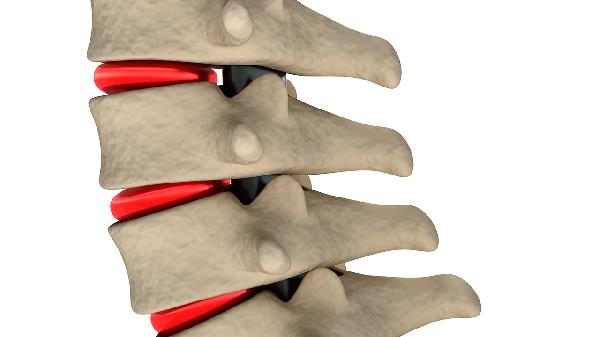

1、体位管理

保持脊柱轴线稳定是核心原则。需使用硬板床,仰卧时在伤椎下方垫软枕维持生理曲度,侧卧时用枕头支撑背部避免扭转。每2小时协助轴向翻身一次,头颈肩腰臀需同步转动,禁止腰部单独扭转。床尾可抬高15度减轻脊柱压力。